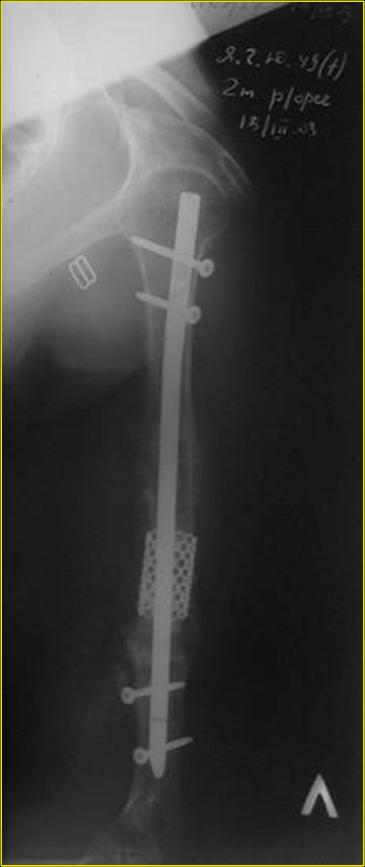

Типичная положительная ситуация для интрамедуллярного остеосинтеза с

использованием опорного металлокаркаса для компенсации дефекта.

Рентгеновская версия реконструкции. хронология:

после операции, 2 мес. после операции, через 1 год

Движения в полном объеме восстановлены к 2 мес. после операции. Если надо могу показать мультик. Сейчас уже прошло более 3 лет, больная не

показывается. Успехов ЛАФ.